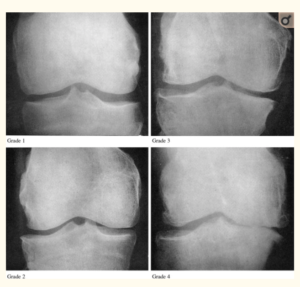

Kellren/Lawrence Scale

Knee replacement surgery is typically reserved for those with end-stage knee arthritis, Kellgren/Lawrence grades 3 or 4 as observable on x-rays. This makes complete sense. Surgically altering your knee, an irreversible act, should be the last resort and only undertaken when all conservative alternatives have been exhausted.

What if I told you that in a recent study of one orthopedic practice at least 19 people who had undergone knee replacement surgery in a one year period were found to have only grade 1-2 Kellgren/Lawrence scores. [4] These patients had persistent knee pain issues that were unexplained at follow-up one year post operation.

In another study, researchers determined that one third of participants had inappropriate surgery based on commonly accepted criteria, like the Kellgren/Lawrence noted above and other clinical measures. [5]

Compassionate medical personnel are stepping up to help these “end of the pipeline” osteoarthritis sufferers resolve this dilemma even if it means doing the replacement when they are only technically grade 1 or 2 Kellgren/Lawrence.